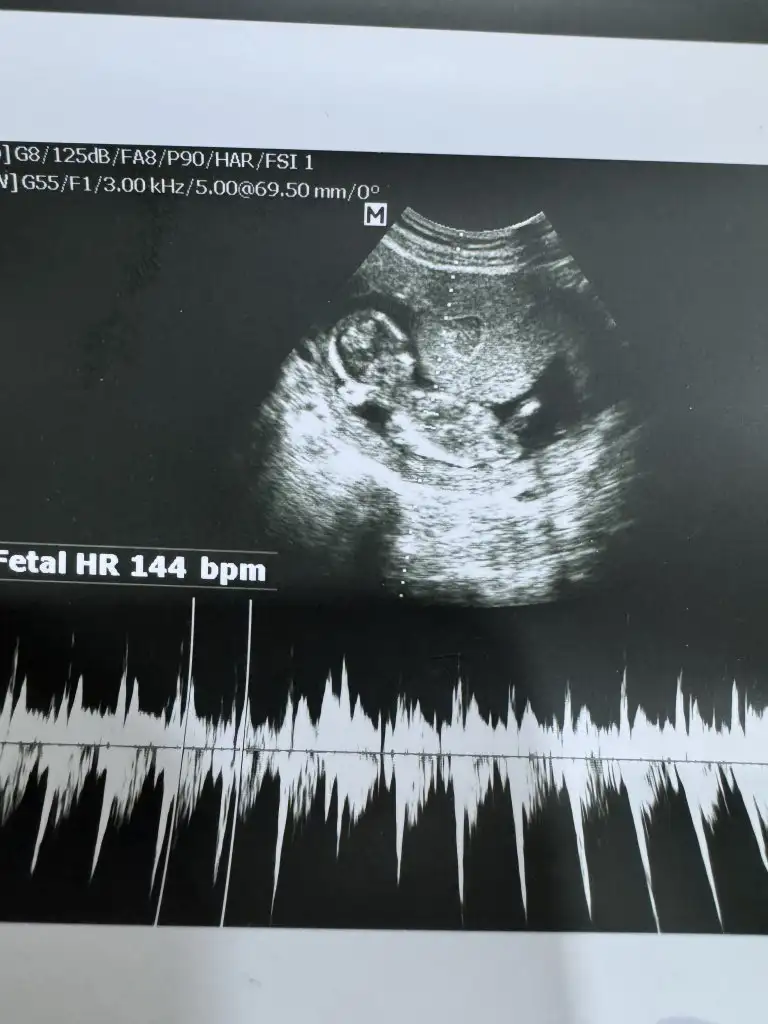

Kız olursa mezhanesi karşıya bakıyor erkek olursa yukarıya bakıyor . Pipiyle alakalı değil yani . Hayırlı Salih kullarından eylesin Rabbim sağlıcakla kucağınıza alın ınsallah . Bende bugün ilk kez kalbînı dinledimErkek dedi doktorumBütün her sey kız gibi gorünüyodu yemekten hareketliligime kadar süpriz yaptı